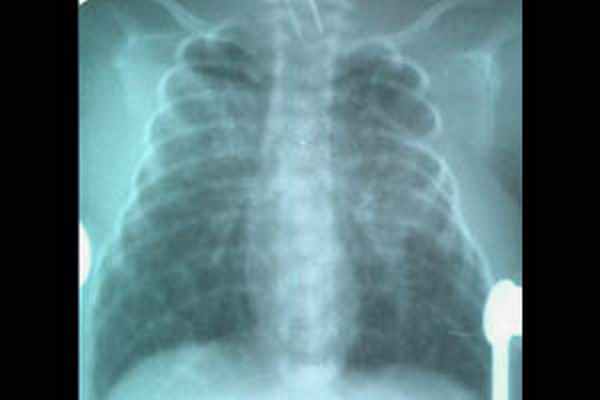

- Рентгенография ОГК. На рентгенограмме неонатолог обнаруживает просветление по периферическим отделам грудной клетки и спадение (коллапс) легкого. При этом средостение, как правило, смещено в здоровую сторону. Рентгенологическое исследование также применяется для диагностики пневмоперикарда.

Неадекватная вентиляция приводит к дыхательной недостаточности. Кожа новорожденного приобретает синюшный оттенок в области носогубного треугольника и кончиков пальцев, при нарастании гипоксии формируется тотальный цианоз. При массивном пневмотораксе пораженная сторона грудной клетки выбухает, отмечается заметная асимметрия. Возникают сердечно-сосудистые нарушения: тахикардия, артериальная гипотония.

Пневмоперикард